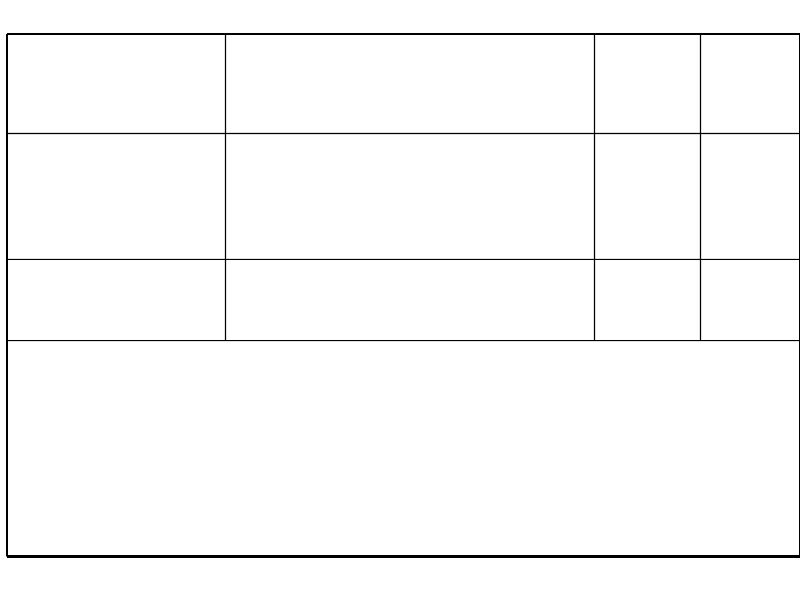

Время удвоения лимфоцитов менее 6 месяцев Время удвоения лимфоцитов более 6 месяцев Стадия на момент диагноза III – IV / C (Rai / Binnet) Возраст менее 65 лет I – II / A Возраст более 65 лет ZAP-70 < 20% Соматическая мутация (-) Соматическая мутация (+) 17 p делеция (p 53 мутация), 13 q делеция 11 q делеция, 12 q трисомия CD 38 (+) CD 38 (-)

Факторы, влияющие на выбор терапии больных ХЛЛ